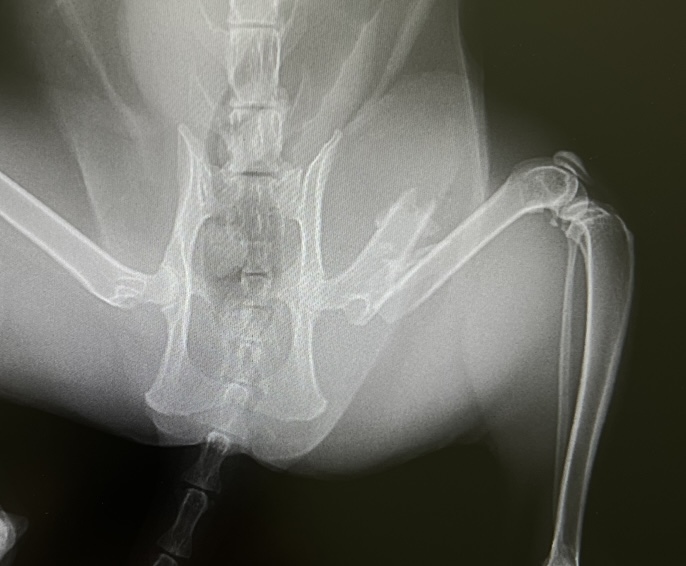

すぐに動物病院に連れて行き、レントゲンをとった結果、左後脚が斜骨折。

その拍子で皮膚から骨が突き出した形跡があり、体も打撲している為、

交通事故による骨折だろうと診断されました。

骨が斜に長く折れているのでプレートで固定をすることができない為、

ピンを入れる手術を行いました。

しばらく薬の投与と手術をした際に入れたピンが飛び出してきたり、骨にヒビが

入らないように小さめのゲージで安静にしながら過ごしています。

3か月ほどしたら診察とレントゲン撮影で、問題が無ければピンを抜く為の再治療になる予定です。